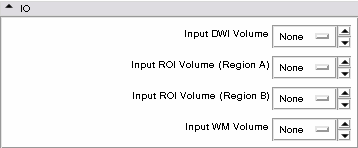

- IO panel: